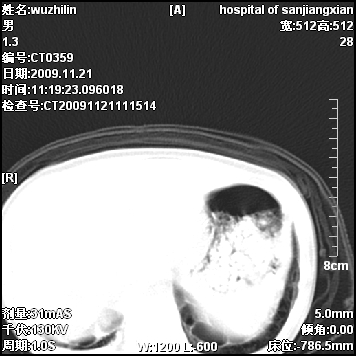

标题: PED3072: 1岁3个月患儿 胸部弥漫性病变 [打印本页]

标题: PED3072: 1岁3个月患儿 胸部弥漫性病变

弥漫性薄壁囊腔,胸膜下及肺底部占优势,双上肺磨玻璃密度影,首先考虑特发性肺间质纤维化,其次囊性肺纤维化,肺淋巴管平滑肌瘤病嗜酸性肉芽肿等;要结合临床综合考虑。

两肺布满多个薄壁含气囊腔,以下肺居多,伴磨玻璃样密度影,左侧气胸。两肺发育不全、两肺多发肺囊肿并感染,其次考虑肺囊腺瘤。